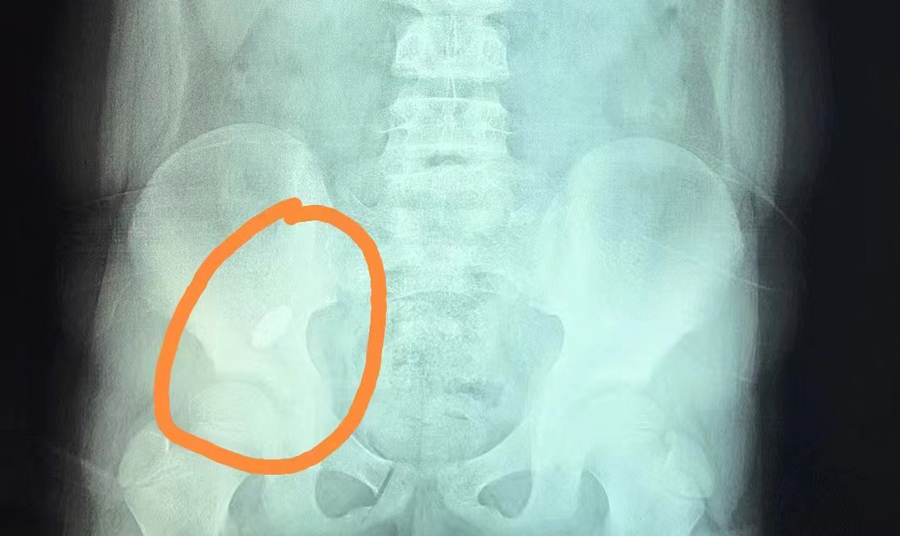

提醒那些认为孩子大了,就可以放松看管的家长:前段时间,长春8岁男孩俊俊(化名)因误吞一颗吸铁石,被家长紧急送到啪啪网 。内镜中心副主任边鹏首先对俊俊开具X线检查,确定异物位于右下腹。随后,她综合俊俊身体及异物情况,提出了先观察的建议,看异物是否能被排出,但是在俊俊复查时,发现异物位置并无变化。考虑到异物可能卡在回盲瓣且时间久,会导致局部黏膜损伤,边副主任建议手术取出异物。3月21日13时许,经过术前准备,内镜中心团队为俊俊进行全麻下异物取出手术。随着肠镜的深入,操作医生看到异物一半卡在了阑尾开口处,便利用异物网兜将异物取出,整个过程仅20分钟。阑尾开口处除了有充血水肿外,无其他异常。经过2天的住院治疗,俊俊痊愈出院。

俊俊算是比较幸运的,因为他吞下的是长约40mm、宽约10mm的椭圆形吸铁石,形状比较圆润,取出也算及时,对黏膜损伤不大。边副主任介绍,内镜中心接诊过各种各样的异物病例,总体看没有尖、刺、刃、毒、腐蚀性的异物,多为形状规则圆润且不太大的消化道异物,相对安全一些。如果异物能自然排出最好,反之则需及时通过镜下取出。